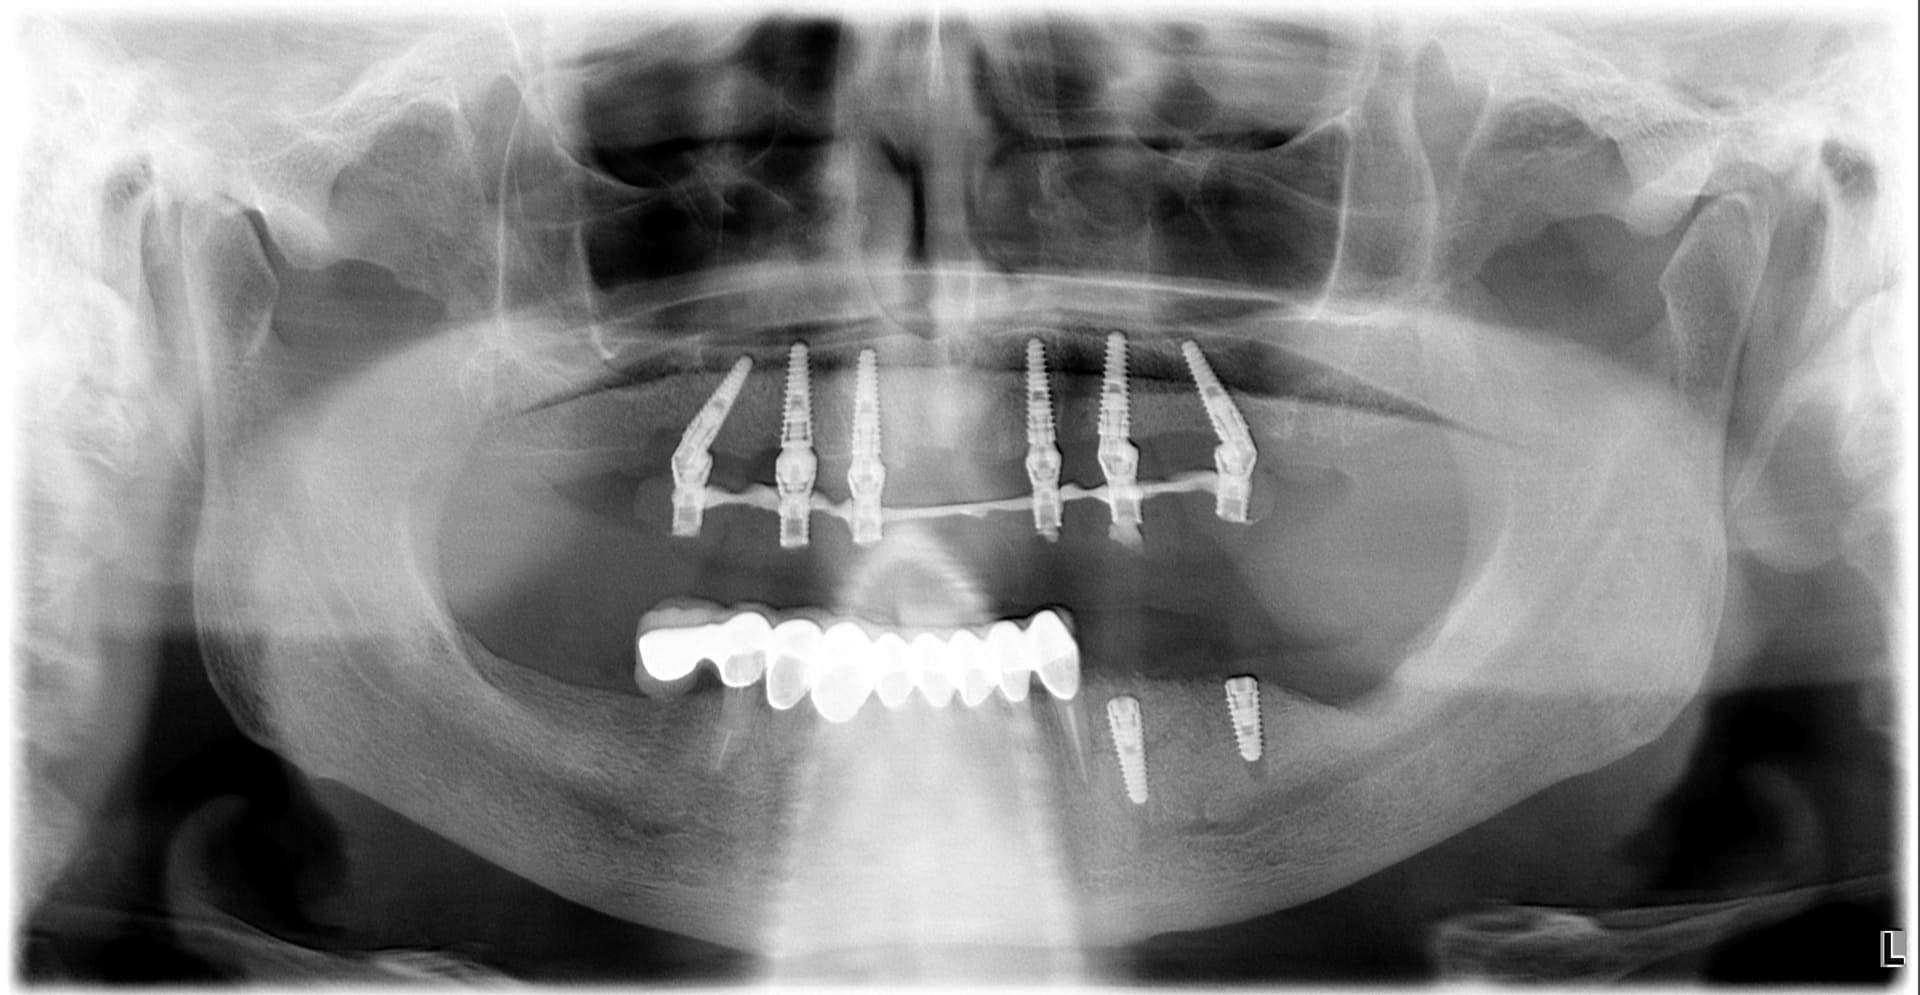

Casi clinici

Paziente 3

< Prima

Dopo >